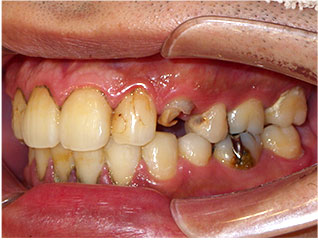

- ブリッジ 症例写真 B-0093スタンダードジルコニア9本、スタンダードジルコニア7本 男性モニターの方です。

Before

After詳細はコチラ

セラミック法によるブリッジ治療の症例

- No. B-0093

施術 スタンダードジルコニア9本、スタンダードジルコニア7本 - コメント

この方は前歯の歯並びと奥歯の虫歯、欠損の治療を希望されました。

前歯の歯並びはセラミック法で治療しました。

奥歯の欠損はブリッジで治療しました。

また、下の前歯も歯周病で1本抜歯になりましたのでその部分もブリッジ治療しています。

当院ではこの様にいろいろな歯のお悩みがあっても同時進行で治療する事が可能です。